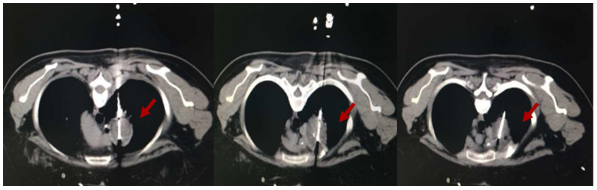

2014-2-25复查胸部CT示:右肺尖见不规则分叶状团块影,大小4.6cm×3.7cm,边缘见毛刺,局部胸膜粘连,考虑肿瘤性病变。2014-3至2014-5 行FOLFIRI方案化疗6周期。2014-8 复查胸部CT示右肺尖肿物较前略增大。2014-9-29 程志强教授于CT引导下行肺部病损氩氦刀手术。术后口服卡培他滨维持治疗,并口服中药治疗。(PFS 1年)

图1 CT引导下肺转移灶氩氦刀冷冻消融术